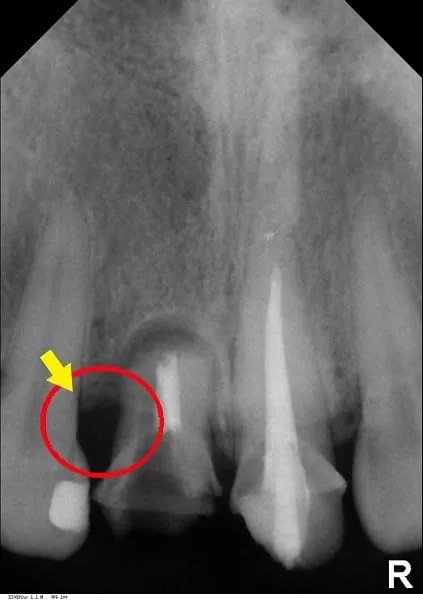

醫師說比較最初與植牙後的X片,可見到當初不僅完整保留原來的骨質,並且再生手術引出更多的骨質,如此牙齦才能塑型到對稱、漂亮。我覺得很幸運可以來這邊將牙齒恢復美觀,從此可以擺脫"掉門牙"的惡夢,真的非常感謝敦南麗緻牙醫診所。